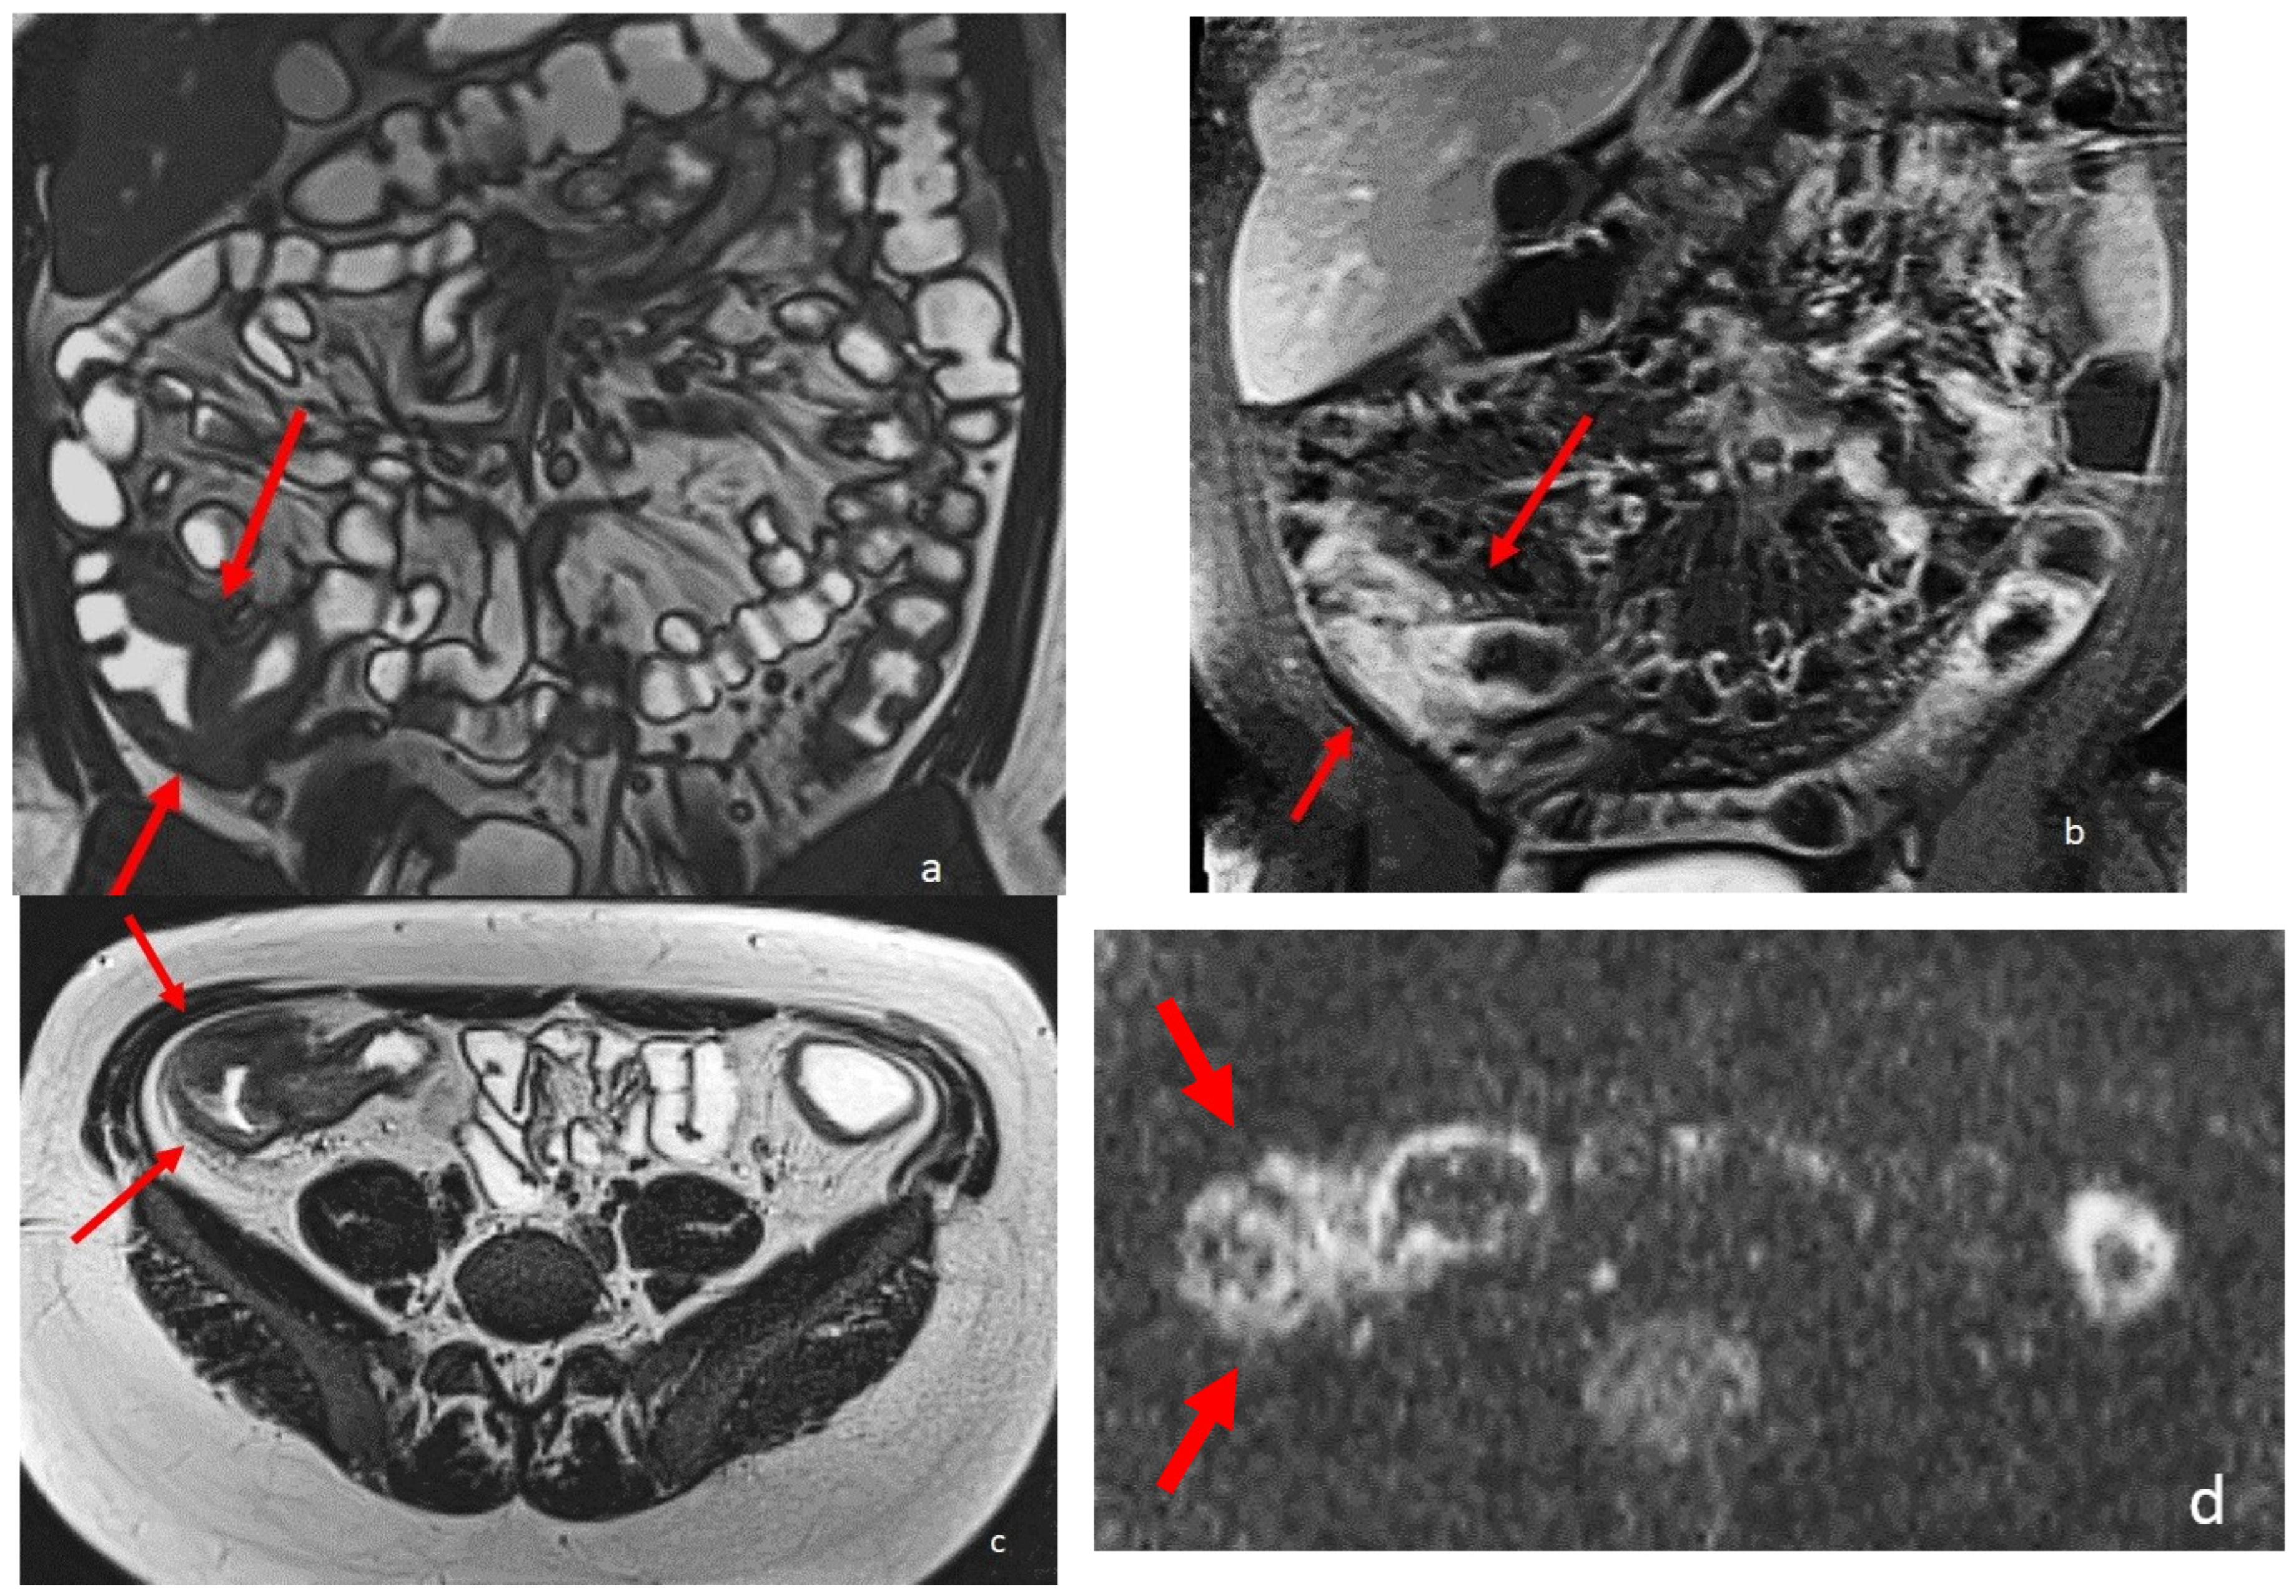

Figure 2.

An eighteen-year-old patient with Crohn’s disease; the arrows point to the wall involvement of the last ileal loop and caecum with wall thickening, post-contrast enhancement, and restricted diffusion. (a) is a coronal TrueFISP image; (b) is a coronal contrast-enhanced T1 weighted image; and (c) is an AxialT2 W high-resolution BLADE image. (d) Axial DWI b800.